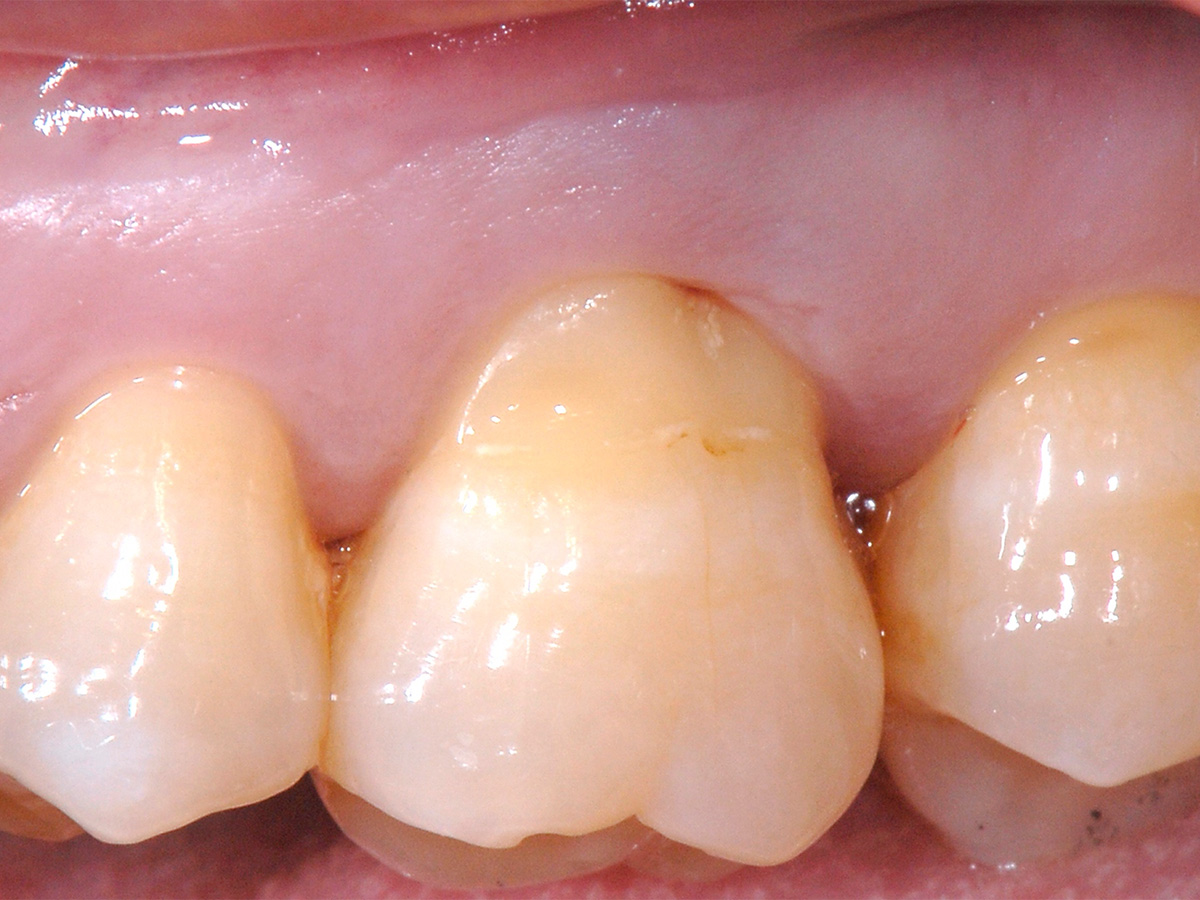

Abbildung 1

Klinische Ausgangssituation: Ausgedehnter parodontaler Furkationsdefekt an Zahn 26 in Kombination mit marginaler Gingivarezession.